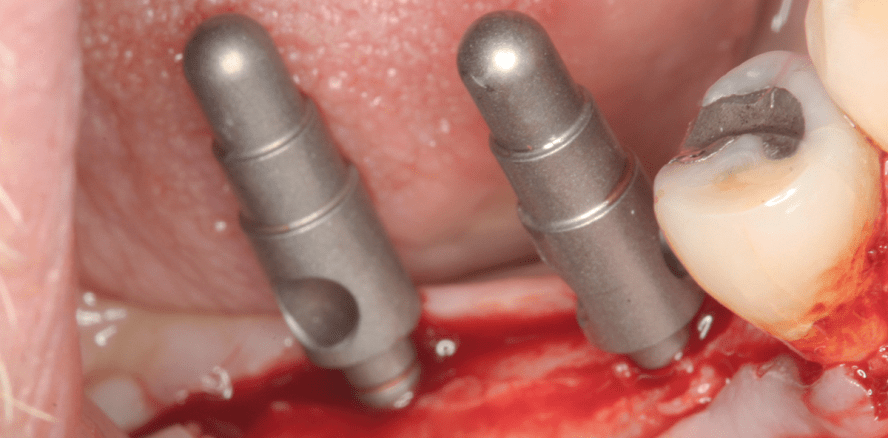

Im iSy Implantatset sind unter anderem das Implantat und ein Einpatienten-Formbohrer enthalten. Das Bohrprotokoll beim iSy System ist bewusst reduziert gehalten. Durch die besondere Bohrerkonfiguration wird nach der 2,8 Millimeter Pilotbohrung sofort der Finalbohrer des jeweiligen Implantatdurchmessers verwendet. Die steril verpackten Bohrer wurden mit dem Winkelstück berührungsfrei aus dem Halter entnommen und das Implantatbett in Regio 46 auf 3,8 Millimeter und in Regio 47 auf 4,4 Millimeter final aufgeweitet (Abb. 5). Da der kortikale Knochen im vorliegenden Patientenfall einer Knochendichte 2 entsprach, benutzten wir einen Gewindeschneider, um den Eindrehwiderstand zu verringern und dadurch einer Nekrose entgegenzuwirken (Abb. 6). Das iSy Implantat wird vormoniert auf der Implantatbasis geliefert. Das Implantat wurde mit dem Eindrehinstrument, das mit leichtem Druck in die Implantatbasis einrastet, aus der Sterilverpackung entnommen, in den Operationsbereich übertragen und inseriert (Abb. 7). Wegen des vorgeschnittenen Gewindes musste darauf geachtet werden, dass die Positionen der Gewindeansätze in der Kortikalis und am Implantat übereinstimmen. Die Implantatschulter wurde epikrestal platziert und eine Fläche des Sechskants nach bukkal ausgerichtet. Zur optischen Kontrolle der korrekten Ausrichtung dient eine Fläche an der Implantatbasis, die mit der Fläche des Sechskants korrespondiert (Abb. 8). Der zylindrische Gingivaformer aus PEEK, enthalten im Implantat-Set, wurde mithilfe des Handgriffs für Gingivaformer auf die Implantatbasis geklickt (Abb. 9). Anschließend wurde das Implantat in Regio 47 auf die gleiche Weise inseriert und der Gingivaformer aufgesteckt (Abb. 10 und 11). Die in den Spiralen der Formbohrer gewonnenen Knochenspäne (Abb. 12) verwendeten wir zur lateralen Knochenanlagerung (Abb. 13). Mit nicht resorbierbaren Einzelknopfnähten (RESORBA 5.0) verschlossen wir den OP-Bereich und ließen die Implantate, dem iSy Konzept folgend, offen einheilen (Abb. 14).

Da der Patient keine provisorische Versorgung wünschte, begannen wir mit der definitiven prothetischen Versorgung zehn Wochen nach dem chirurgischen Eingriff. Zum Zeitpunkt der Abformung zeigte sich eine ausreichend stabile Attached Gingiva (Abb. 15). Wir entfernten die PEEK Gingivaformer von der Implantatbasis und steckten die Multifunktionskappen, die im Implantat-Set enthalten sind, auf die Basis auf (Abb. 16 bis 18). Mit einem Polyether-Abformmaterial (ImpregumTM Plus, 3M ESPE) und einem geschlossenen Löffel formten wir die Implantatsituation ab. Die Retentionen der Multifunktionskappen sind optimal gestaltet, sodass sie exakt und ohne Verzug im Abformmaterial gehalten werden (Abb. 19). Die beiden weiteren